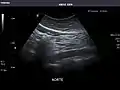

Aorta: Visualized portions normal in caliber, 16 x 15 mm.

Aorta